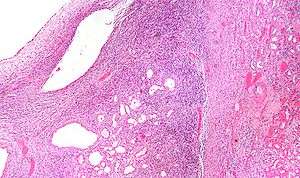

| Micrograph of a cystic nephroma (left of image). Normal kidney is seen on the right. H&E stain. | |

A cystic nephroma, also known as multilocular cystic nephroma, mixed epithelial stromal tumour (MEST) and renal epithelial stromal tumour (REST),[1] is a type of rare benign kidney tumour.